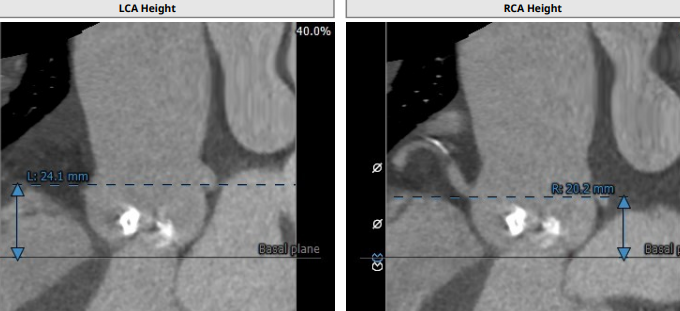

术前CT:

重度钙化Type0型二叶瓣,瓣环面积:481mm²,左室流出道面积:533mm²,左冠开口高度:24.1mm,右冠开口高度:20.2mm。